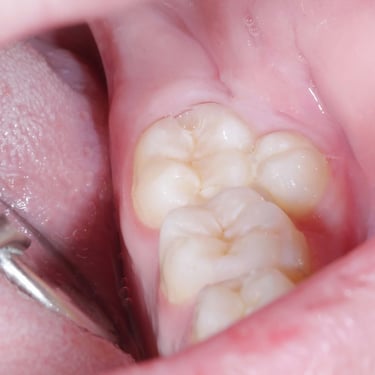

Dientes Supernumerarios

Los dientes supernumerarios son dientes adicionales que pueden aparecer en la boca y causar problemas de alineación o erupción de otros dientes.

Los pacientes pueden notar dientes adicionales en la boca, lo que puede causar apiñamiento o problemas estéticos.

El tratamiento incluye la extracción quirúrgica de los dientes supernumerarios.